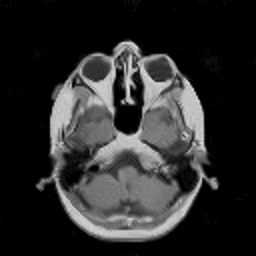

VII-C Experiments with real-life data

Reconstruction of real-life MRI images has been the next step in our comparative study. To this end, the data set of [19] have been used herein. The data were obtained at the University Hospital of Ghent and it is publicly available at http://telin.ugent.be/~sanja/Sanja_files/Software/MRIprogram.zip. The data contains a sagittal and an axial scan of a human brain, which are shown in Fig. 10 and Fig. 11, respectively.

The reconstruction results obtained for each of the tested images using the proposed and reference methods are shown in Subplots (b)-(f) of Fig. 10 and Fig. 11, respectively. From these figures, it can be seen that the proposed algorithms result in higher-contrast reconstructions of better visual clarity as compared to the reference approaches. The difference is particularly evident for the case of Fig. 11, where the proposed algorithms result in less noisy images, while exhibiting higher effective resolution and contrast.

Figure 10: (a) Sagittal MRI scan; (b)-(f) Reconstruction results obtained using TVDN, WDN, GNLM, NLMS and NLMR, respectively.

Refer to caption

Figure 11: (a) Axial MRI scan; (b)-(f) Reconstruction results obtained using TVDN, WDN, GNLM, NLMS and NLMR, respectively.